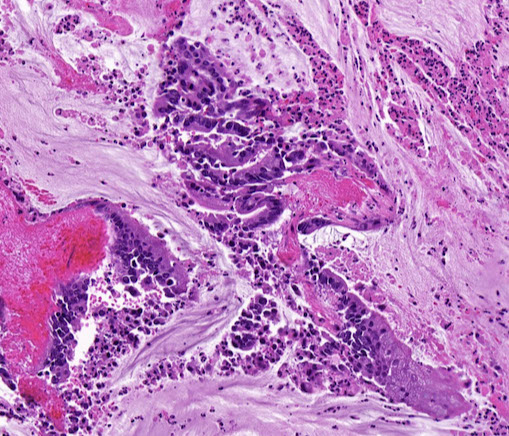

Microscopic pathology of Crohn disease. A, Haphazard crypt organization results from repeated injury and regeneration. B, Noncasearing granuloma. C, Transmural Crohn disease with submucosal and serosal granulomas (arrows)

Microscopically, Crohn disease is characterized by transmural inflammation. Here, inflammatory cells (the bluish infiltrates) extend from mucosa through submucosa and muscularis and appear as nodular infiltrates on the serosal surface adjacent to fat. Note the granulomatous inflammation.